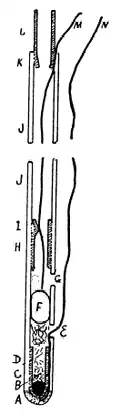

Гастроинтестинальная эндоскопия

Эндоскопические исследования выполняются с помощью специальных аппаратов-эндоскопов, вводимых пациенту через естественные отверстия — рот или задний проход и передающих изображение в исследуемом органе или на окуляр эндоскопа или на монитор. В современной практике используются два типа гибких эндоскопов: волоконно-оптические фиброэндоскопы и видеоэндоскопы, оцифровывающие видимую в объектив картинку и передающие её в таком виде на монитор или окуляр. Эзофаго-, гастро-, дуодено- и/или еюноскопия показаны при подозрении на воспаление или язву, а также другие заболевания пищевода, желудка, тонкой кишки, фатерова сосочка. Колоноскопия — эндоскопическое исследование толстой кишки, показана при наличии клинических признаков, указывающих на поражение толстой кишки, наблюдении за пациентом в процессе лечения, при осмотрах, направленных на выявление на ранней стадии онкологических и других заболеваний[22].

- Эндоскопические исследования пищевода, желудка и кишечника

Гибкий волоконно-оптический фиброэндоскоп

Внутрижелудочная pH-метрия играет важнейшую роль при диагностике и лечении кислотозависимых заболеваний, при исследовании гастроэзофагеальных, дуоденогастральных, фаринголарингеальных рефлюксов. В клинической практике нашли применение несколько методов внутрижелудочной pH-метрии:эндоскопическая (длительность измерений 5 минут), экспресс-pH-метрия (около 30 минут), кратковременная стимулированная (до 2—3 часов) и длительная (24 часа и более) pH-метрия. pH-метрия также применяется для оценки действия кислотоподавляющих препаратов. Измерения выполняется с помощью специальных pH-метрических зондов, вводимых пациенту перорально (при кратковременной pH-метрии), трансназально (при суточной pH-метрии)[21][23], через инструментальный канал эндоскопа (при эндоскопической pH-метрии)[24] или с помощью прикрепляемых к стенке пищевода pH-метрических капсул[25]. Исследование некислых рефлюксов выполняется с помощью импеданс-pH-метрии пищевода[26]. Для дифференциальной диагностики загрудинных болей неясной этиологии применяется гастрокардиомониторинг — одновременное исследование кислотности ЖКТ и электрокардиограммы[21].